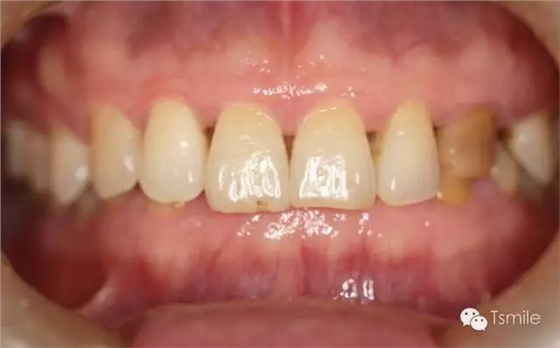

圖2: 前牙功能范圍受限導(dǎo)致的前牙重度磨耗 磨損是指在非下頜功能運(yùn)動(dòng)和副功能運(yùn)動(dòng)中,除牙齒以外的其它物體對(duì)牙齒表面機(jī)械摩擦而導(dǎo)致的牙齒表面硬組織缺損。 磨損患者一般有某種特殊的生活習(xí)慣或工作習(xí)慣,如不正確的刷牙方式、長(zhǎng)時(shí)間叼煙斗、咬指甲、咬鉛筆等生活和工作習(xí)慣。長(zhǎng)時(shí)間的不良習(xí)慣,這些煙斗、鉛筆、指甲等異物會(huì)對(duì)牙齒表面過(guò)度機(jī)械摩擦,導(dǎo)致牙齒表面硬組織缺損。

磨耗患者中還有一類特殊的局限于上下前牙區(qū)的牙齒重度磨耗,表現(xiàn)為上前牙舌面、下前牙切端和唇面的重度磨耗。該類患者常表現(xiàn)為一類特殊的咬合類型,重度深覆頜或者上前牙明顯舌傾,這種咬合類型導(dǎo)致下頜前伸功能運(yùn)動(dòng)受限,從而導(dǎo)致前牙區(qū)重度的磨耗,可稱為前牙功能范圍受限(restricted envelope of function)。